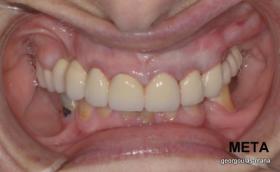

ΑΝΟΙΚΤΗ ΑΝΥΨΩΣΗ ΙΓΜΟΡΕΙΟΥ Κ ΤΟΠΟΘΕΤΗΣΗ 3 ΕΜΦΥΤΕΥΜΑΤΩΝ

Στην ασθενή αυτή πραγματοποιήθηκε ανοικτή ανύψωση ιγμορείου άνω αριστερά. Σε πρώτη φάση πραγματοποιήθηκε η οστική αύξηση και 6 μήνες μετά τοποθετήθηκαν 3 εμφυτεύματα. Τόσο στην πανοραμική όσο και στην τομογραφία κωνικής δέσμης (CBCT) που πραγματοποιήθηκαν 6 μήνες μετά την ανύψωση είναι εμφανής ο σχηματισμός οστού. Η τελευταία ακτινογραφία και φωτογραφία λήφθηκαν 5 χρόνια μετά την προσθετική αποκατάσταση.